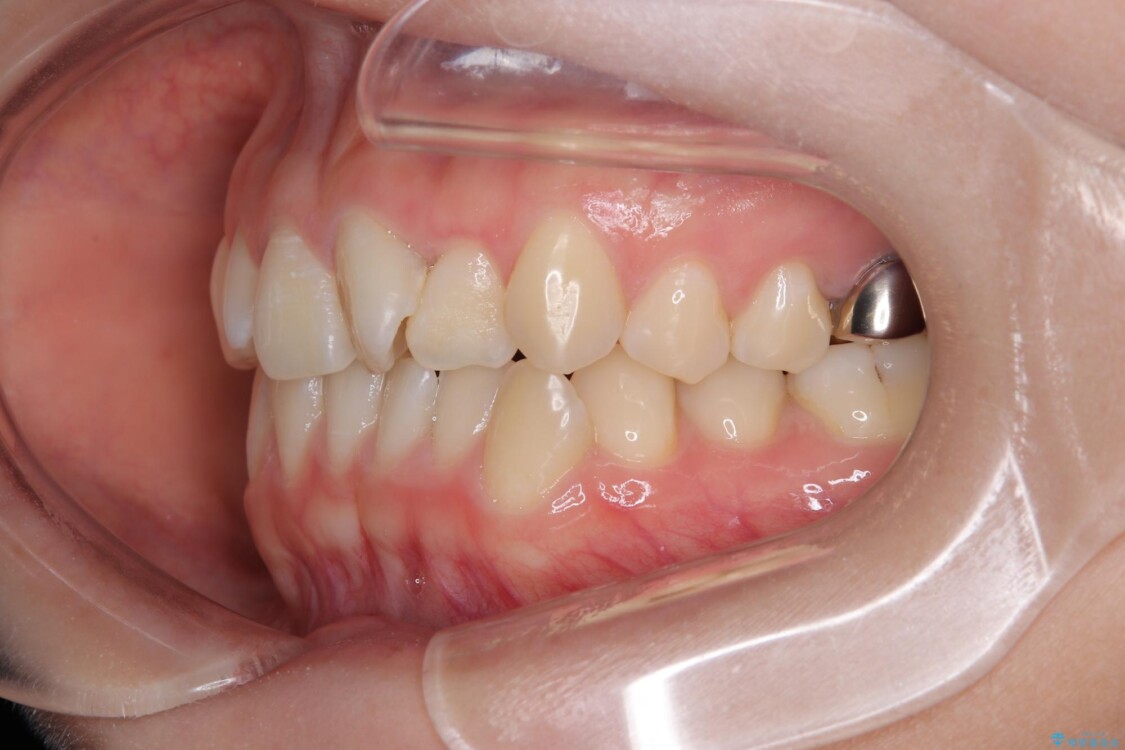

診察の結果、上下の前歯部に**叢生(そうせい/歯のガタガタ・重なり)**が認められました。

特に上の前歯にはねじれや重なりがあり、審美的にも清掃性にも影響している状態でした。

治療前

• 前歯のねじれ・ガタガタを10か月で改善!20代女性の矯正治療|クリアブラケットでむし歯になりにくい歯並びへ改善 治療前画像